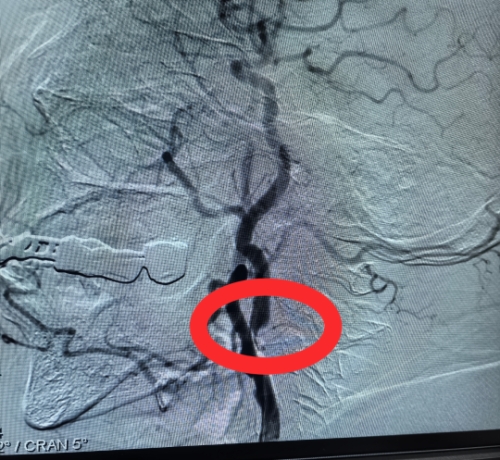

手术过程中,卒中中心脑血管病团队精准操作,在脑保护装置护航下,顺利完成颈动脉狭窄扩张与支架植入,成功打通大脑“供血主干道”。患者术中生命体征平稳,术后即刻血流恢复通畅,头晕、肢体乏力等症状显著改善,康复进程顺利。